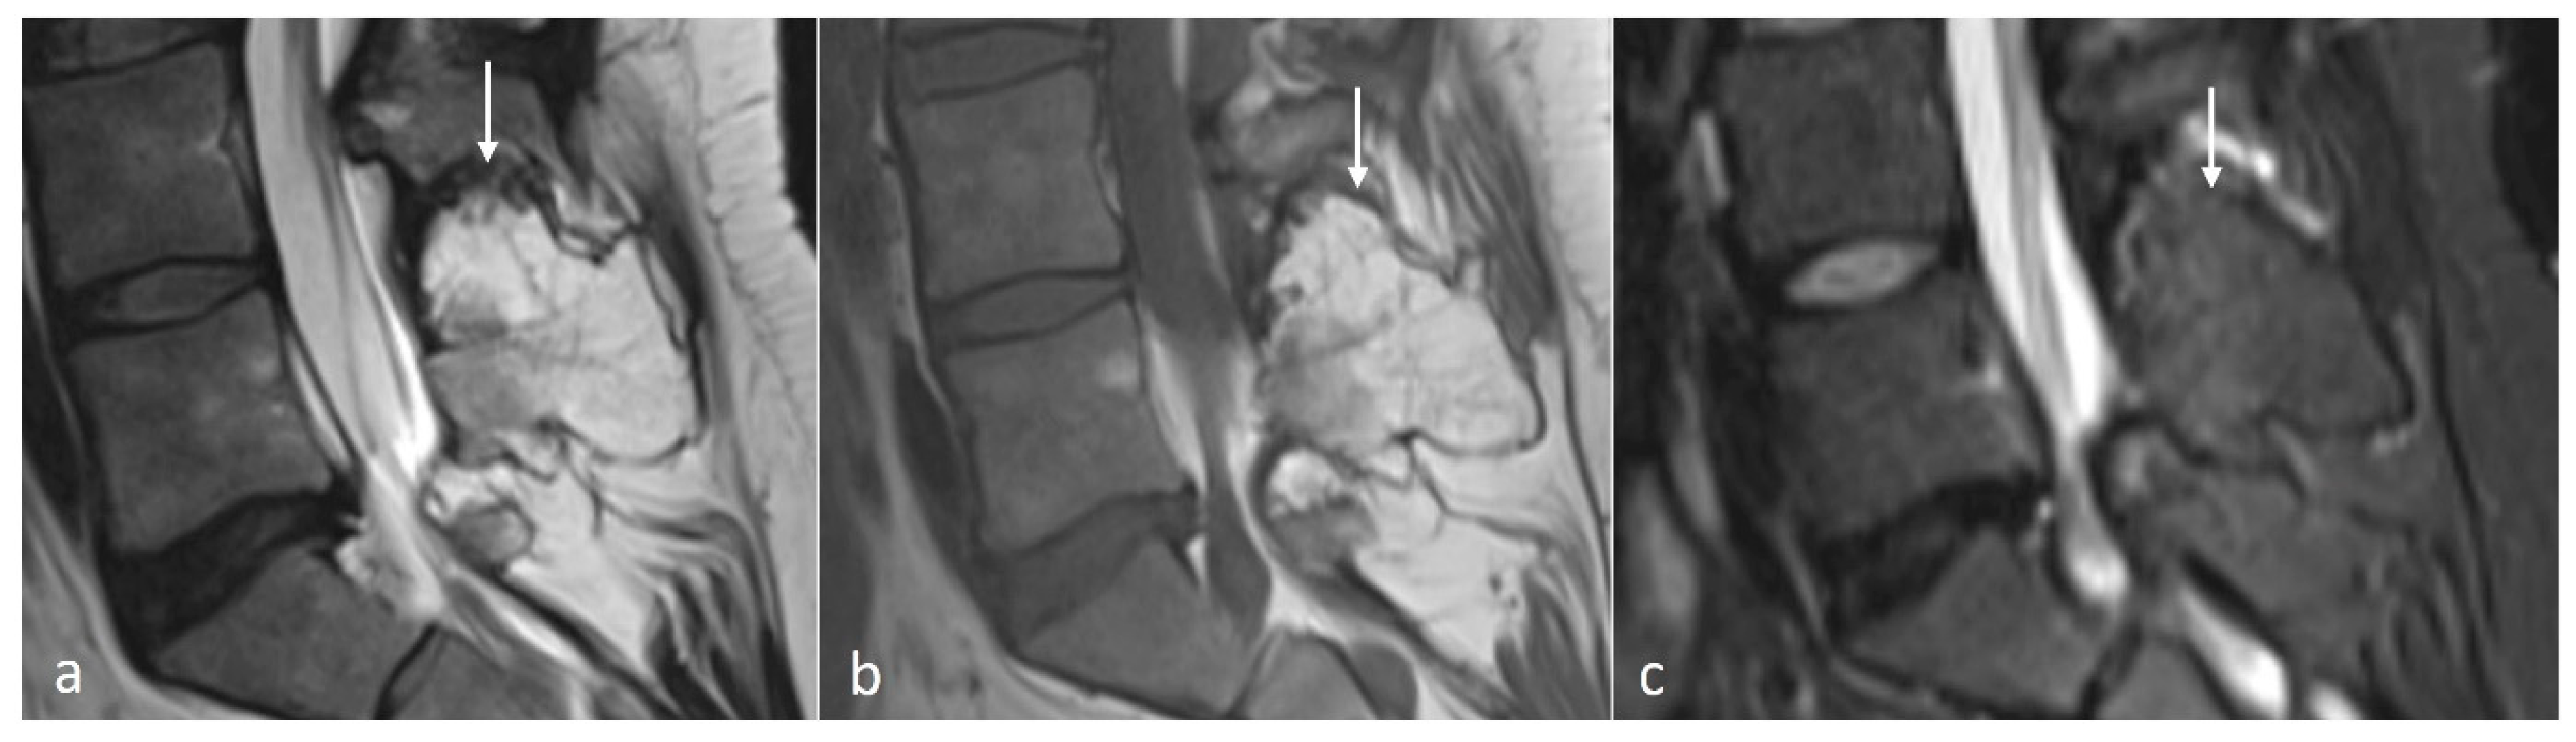

Osteochondroma is a cartilage-capped bony exostosis and the commonest benign bone lesion. They occur spontaneously or in the setting of Hereditary Multiple Exostosis (HME). The majority of spinal osteochondromas occur in the cervical spine [17]. The morphology can be either sessile or pedunculated, and they have a cartilage cap, which is best appreciated on MRI (Figure 3a–c). The cartilage cap usually demonstrates high T2 signal and should be <15 mm in diameter. Increased thickness of the cap can be a sign of malignant degeneration [18].

Figure 3.

Sagittal T2 (a), T1 (b) and STIR (c) images showing an osteochondroma of the L5 spinous process (white arrows). Note the presence of the thin cartilage cap on its superior aspect.